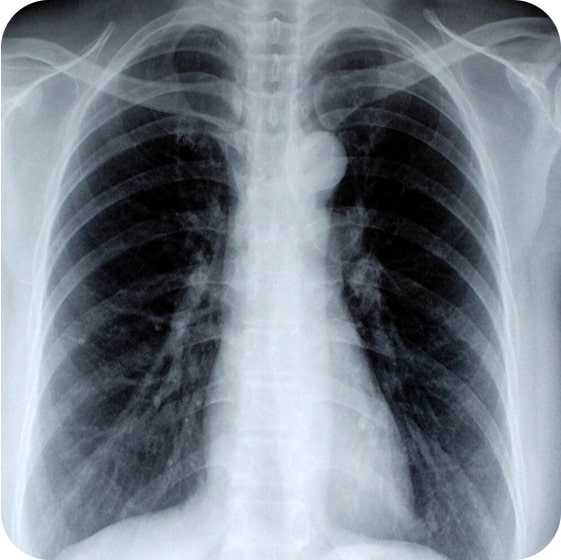

Определить болезнь можно с помощью рентгенографии или компьютерной томографии легких. На снимке будет видно, поражен ли орган.

Рентгенографическое исследование легких

С его помощью можно выявить новообразования и очаги воспалительных процессов.

До лечения

После лечения